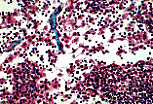

| 此为鸽子足部皮下组织中初级脂肪组织(棕脂)小叶的标本。初级脂肪细胞含有大量不融合的脂滴(在石蜡包埋过程中溶解),因此被称为"海绵细胞", 该脂肪组织也因此被称为 "多泡性"脂肪组织。 细胞核通常位于中央位置。每个脂肪细胞均被基膜和纤细的网状纤维网络包绕。 | |